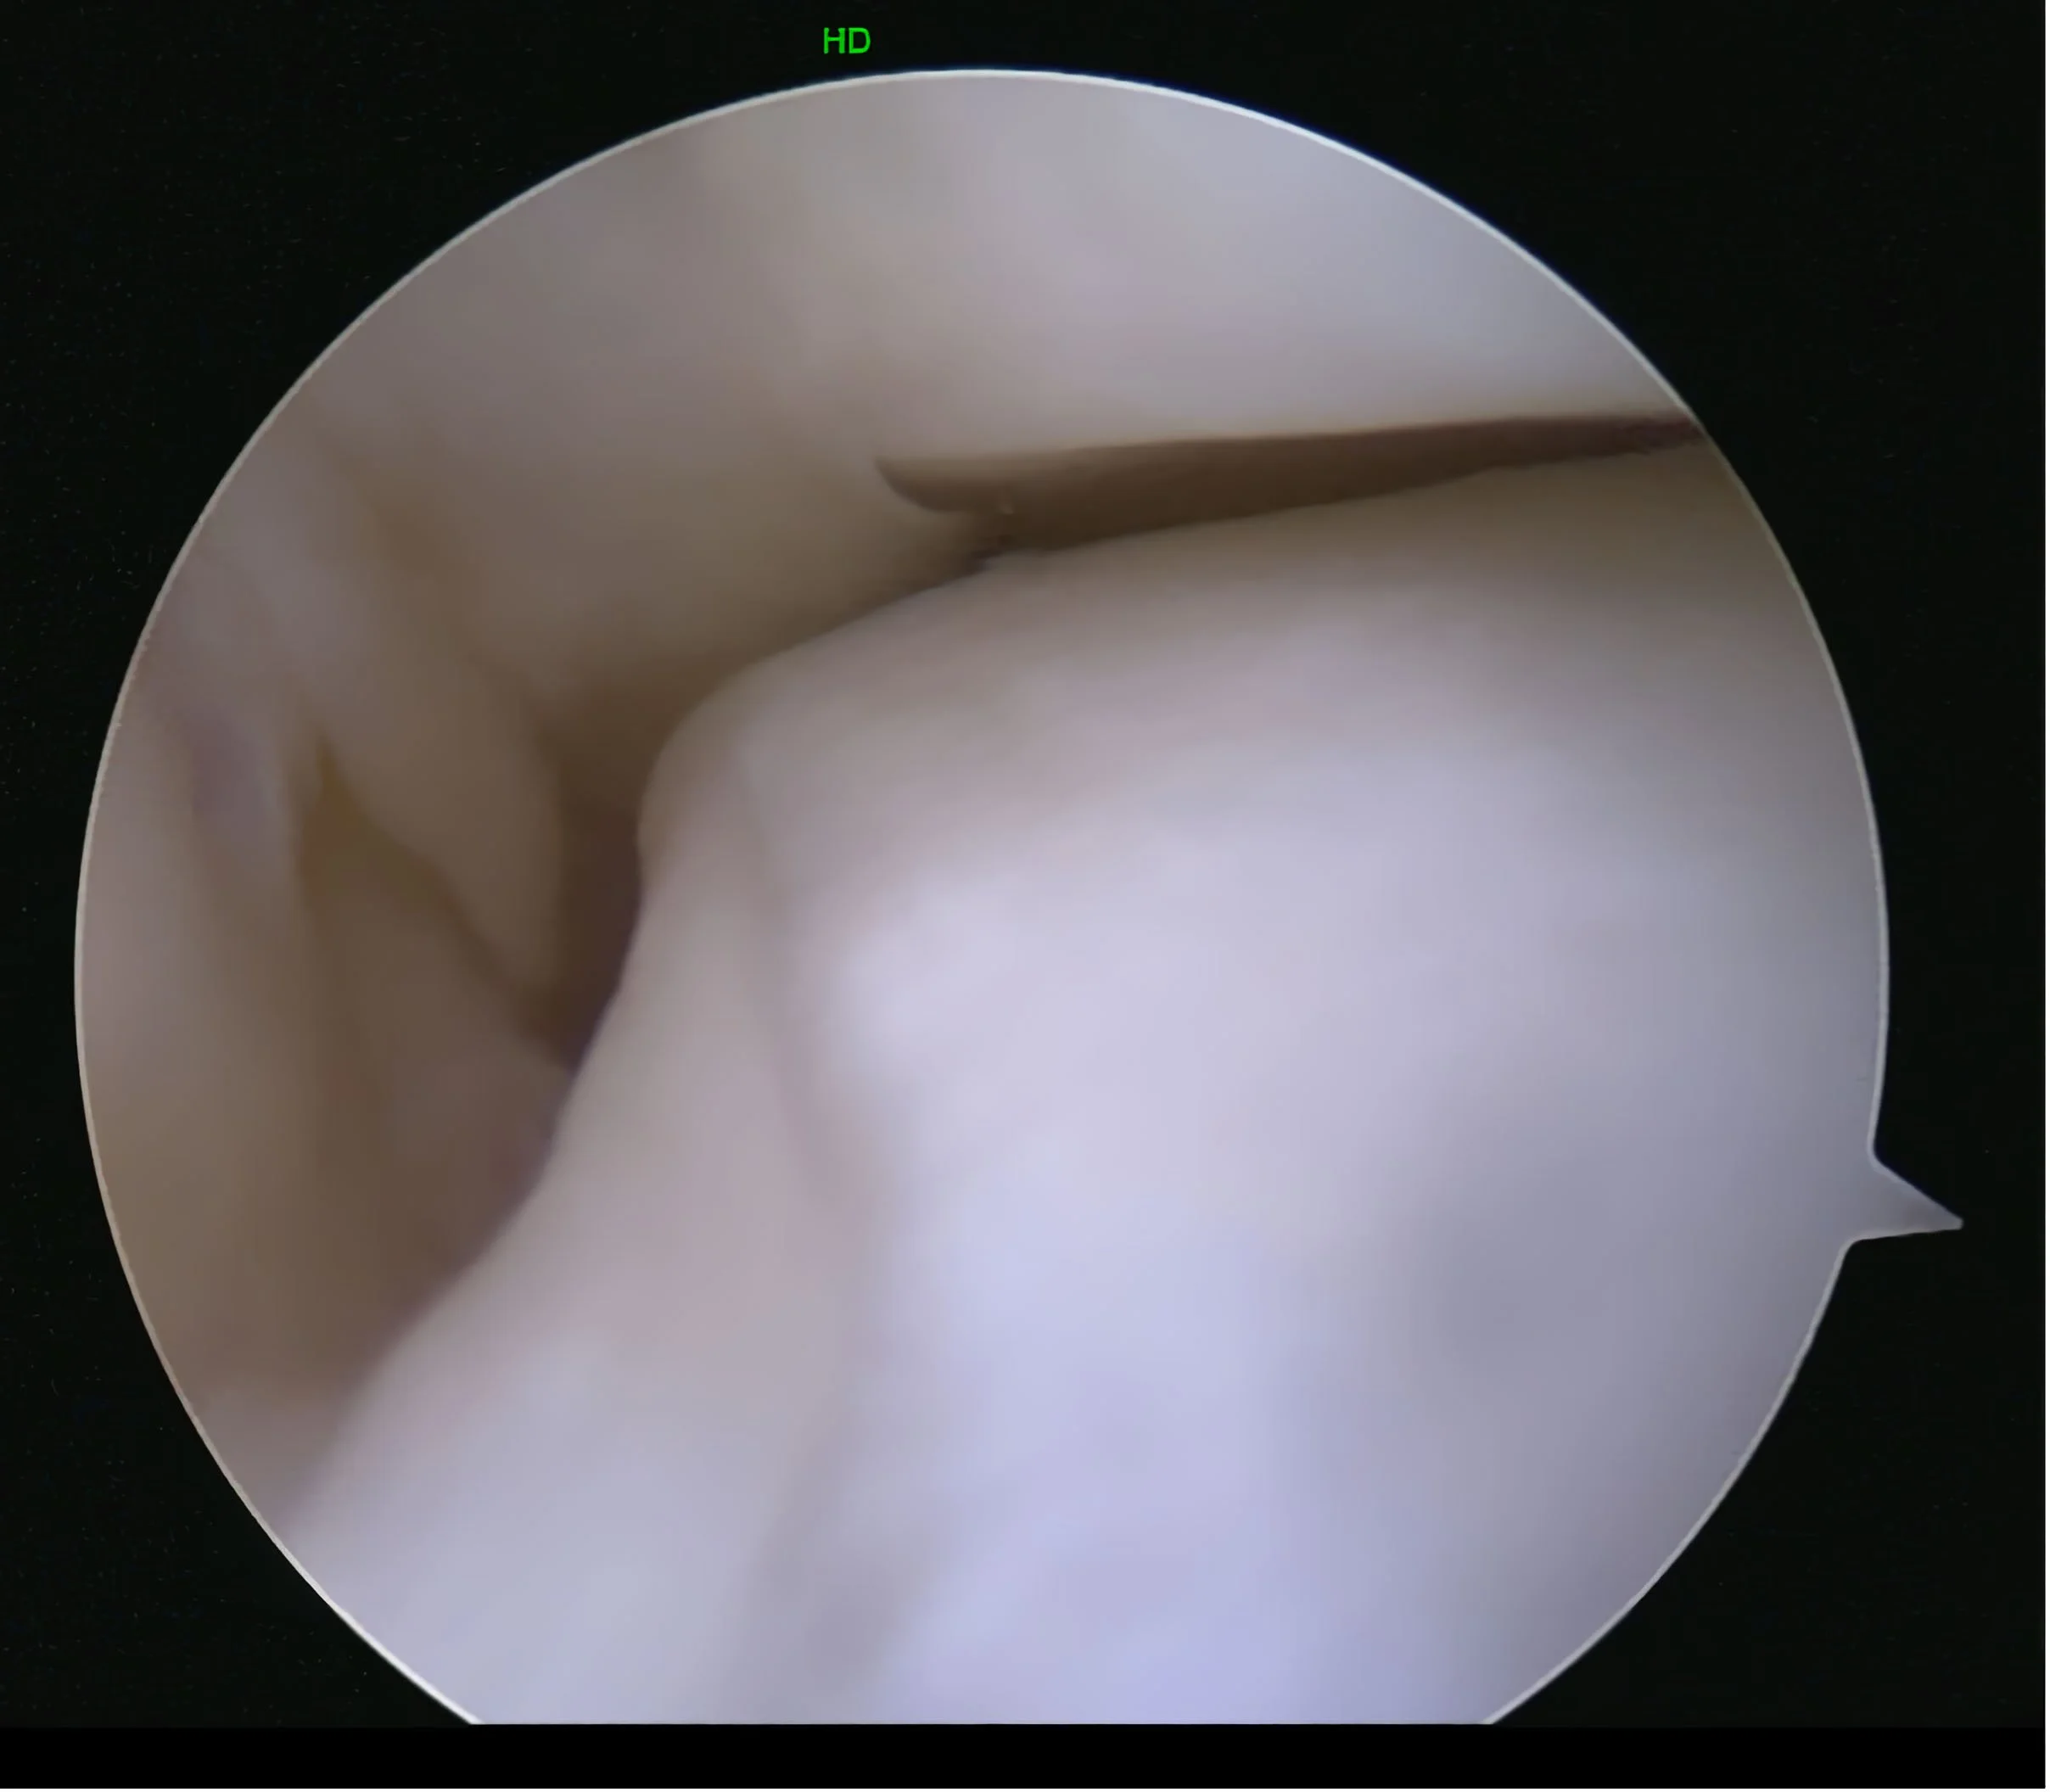

Een kijkoperatie kan aan de voorzijde of aan de achterzijde van de enkel plaatsvinden, maar ook via de zijkant van de enkel, voor het onderste spronggewricht. De operatieduur is een beetje afhankelijk van wat er precies moet gebeuren en kan variëren van 15 minuten tot meer dan een uur. Voor de operatie is een goede verdoving nodig, en deze bestaat meestal uit een ruggenprik of een algemene narcose.

Er zijn verschillende klachten die door middel van een kijkoperatie worden behandeld. Er worden twee kleine sneetjes van ongeveer een halve centimeter aan de voorzijde van de enkel gemaakt. Vooral het sneetje aan de buitenzijde kan na de operatie pijnklachten opleveren.

Tijdens de operatie wordt er vocht in het gewricht gepompt. Hierdoor ontstaat er wat meer ruimte en kan de operatie veilig worden uitgevoerd. Het betekent natuurlijk wel dat de enkel na de operatie dik is, dit kan lange tijd aanhouden en is niet verontrustend.